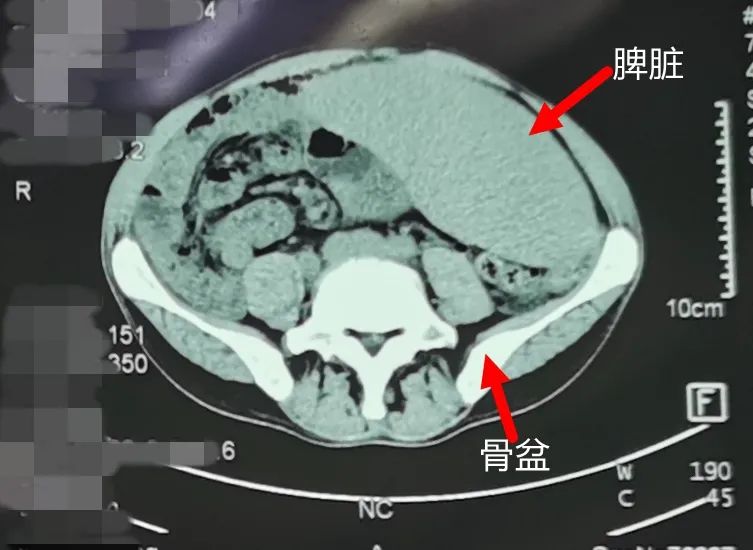

CT檢查結(jié)果顯示,劉先生的脾臟已經(jīng)超過(guò)正常人的7倍大,從左上腹一直長(zhǎng)到了右下腹并深入盆腔里,幾乎占據(jù)了他的整個(gè)腹腔,嚴(yán)重壓迫到周?chē)K器和血管?!斑@個(gè)患者的手術(shù),應(yīng)該是醫(yī)院開(kāi)院以來(lái),普外科做過(guò)的最大的脾臟切除,”胡主任說(shuō)。